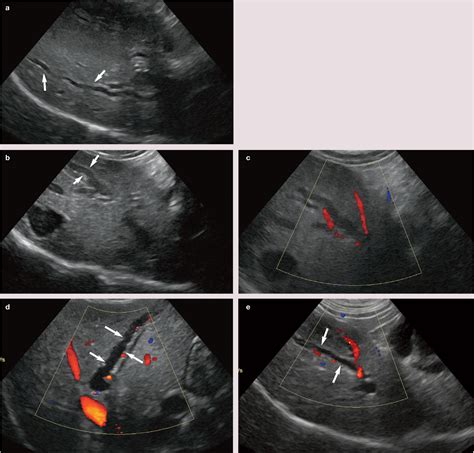

Imaging techniques such as transabdominal ultrasound, magnetic resonance cholangiopancreatography (MRCP), and endoscopic ultrasound (EUS) are commonly used to visualize this structure. When a patient experiences biliary colic or elevated bilirubin levels, clinicians look at the common bile duct size to assess for obstruction. In many cases, a dilated duct is a clear indicator that something is physically blocking the passage, causing bile to "back up" into the liver.

If a doctor suspects an issue with the bile duct, they will choose an imaging modality based on the patient's symptoms and initial findings. Ultrasound is typically the first-line, non-invasive method used to screen for common bile duct size. It is quick and avoids radiation exposure.

However, if ultrasound is inconclusive or if there is a strong suspicion of stones or tumors, more detailed imaging is required. MRCP is a highly specialized, non-invasive MRI technique that provides excellent visualization of the entire biliary tree without the need for contrast agents or invasive procedures. In cases where intervention is required—such as removing a stone or placing a stent—Endoscopic Retrograde Cholangiopancreatography (ERCP) is performed, which combines endoscopic visualization with fluoroscopic imaging.